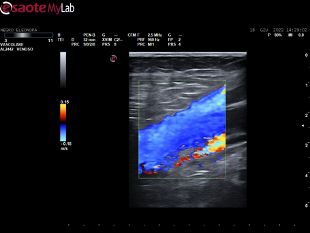

Svolgo attività quotidiana di diagnostica vascolare non invasiva, di cura delle arteriopatie e di tutte le patologie venose: varici, trombosi venose profonde acute, sindrome post-trombotica, ulcere venose e/o linfatiche, edemi degli arti inferiori, ulcere croniche.

• Ecocolordoppler vascolare

120 €